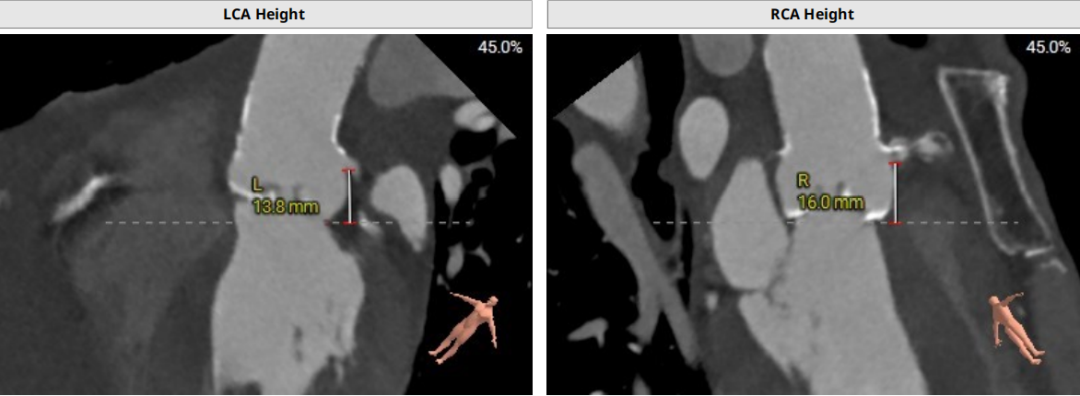

术前CT评估示

近日,中国人民解放军南部战区总医院王显悦教授、张本教授团队应用J-VALVE瓣膜完成一例高难度经心尖TAVI。患者为72岁男性,心脏超声示主动脉瓣重度狭窄伴轻度关闭不全,且二尖瓣中度狭窄。由于具有急性心力衰竭、高血压3级、肺气肿等其他疾病,且体重仅35公斤,对外科开胸手术耐受较差,风险极大,经过团队综合评估,决定行经心尖TAVI手术,拟植入25mm J-VALVE瓣膜。该患者存在升主动脉瓷化和左室流出道重度钙化,为手术增加了额外难度,术者团队凭借过硬的专业技能和细节处理能力,有效避免了术中可能存在的风险,并成功植入瓣膜。术后食道超声示无瓣周漏、无冠脉堵塞等并发症,患者症状明显缓解,手术顺利完成。